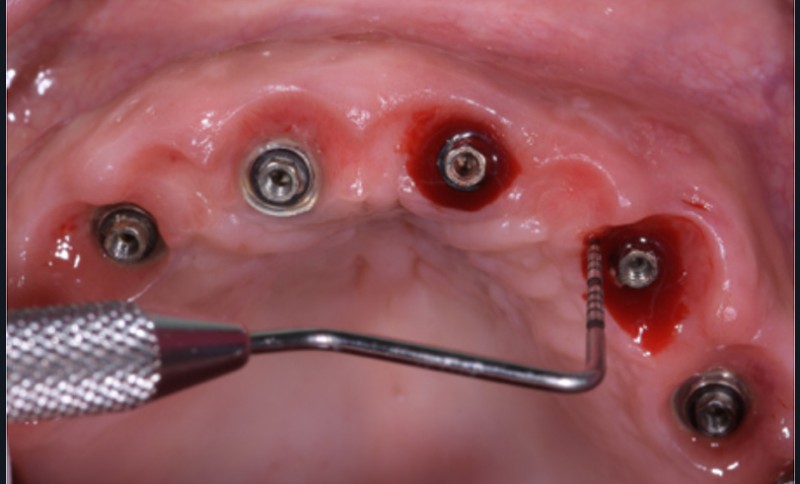

2 – Une méta analyse de 2016 [3] a évalué l’efficacité du traitement non chirurgical de la péri-implantite. Il s’avère que le traitement non chirurgical ne permet qu’une diminution de l’inflammation au niveau des tissus mous à court terme. En effet, on observe une diminution significative du saignement au sondage, mais pas de diminution efficace de la profondeur de sondage. En revanche, sans traitement chirurgical, on note une progression importante de la perte osseuse. Le traitement non chirurgical…